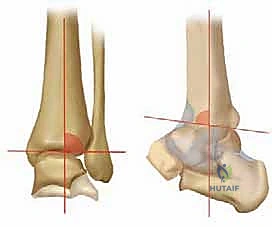

فهم خشونة مفصل الكاحل من النوع التقوسي (Varus Ankle Osteoarthritis)

خشونة مفصل الكاحل من النوع التقوسي هي حالة مرضية تدريجية (Progressive) لا تحدث بين عشية وضحاها. إنها تتميز بتشوه تقوسي مع فتح أمامي للسطح المفصلي في الطرف البعيد من عظم الساق. وغالباً ما تظهر هذه الحالة بشكل ثنائي (في كلا الكاحلين)، وتكون أكثر شيوعاً لدى النساء في منتصف العمر وكبار السن، وكذلك لدى الرياضيين السابقين أو الأشخاص الذين تعرضوا لإصابات قديمة.

| المرحلة الأولى (المبكرة) | لا يوجد تضيق ملحوظ في المسافة المفصلية. ظهور تصلب عظمي مبكر (Sclerosis) وتكون نتوءات عظمية صغيرة (Osteophytes) في الزاوية الأمامية الإنسية. | الغضروف لا يزال سليماً بنسبة كبيرة، المسافة المفصلية طبيعية. | ألم خفيف بعد المجهود الطويل، تيبس بسيط في الصباح. |

| المرحلة الثانية (المتوسطة) | تضيق واضح وغير متماثل في المسافة المفصلية، يتركز بشكل أساسي في الجانب الإنسي (الداخلي) للكاحل. | ترقق ملحوظ في الغضروف الداخلي، بداية احتكاك غير مباشر. | ألم متكرر مع المشي، تورم متقطع، بداية ملاحظة ميلان القدم. |

| المرحلة الثالثة (المتقدمة) | طمس شبه كامل للمسافة المفصلية مع تلامس العظم تحت الغضروف في الجانب الإنسي. تنقسم إلى: 3أ: الطمس يقتصر على وجه الكعب الإنسي. 3ب: الطمس يمتد لسقف قبة الكاحل. |

تآكل شديد للغضروف، احتكاك مباشر للعظم بالعظم في الجانب الداخلي. | ألم شديد يعيق الأنشطة اليومية، تورم مزمن، عرج واضح أثناء المشي. |

تكمن المشكلة الأساسية في خشونة مفصل الكاحل من النوع التقوسي في تركز الإجهاد على الجانب الإنسي. هدف جراحة قطع العظم التي يجريها الدكتور هطيف ليس فقط إيقاف هذا التدهور، بل وإعطاء الجسم فرصة لإصلاح عيوب الغضروف جزئياً عن طريق تشكيل نسيج غضروفي ليفي (Fibrocartilage) بمجرد إزالة الضغط الميكانيكي عنه.